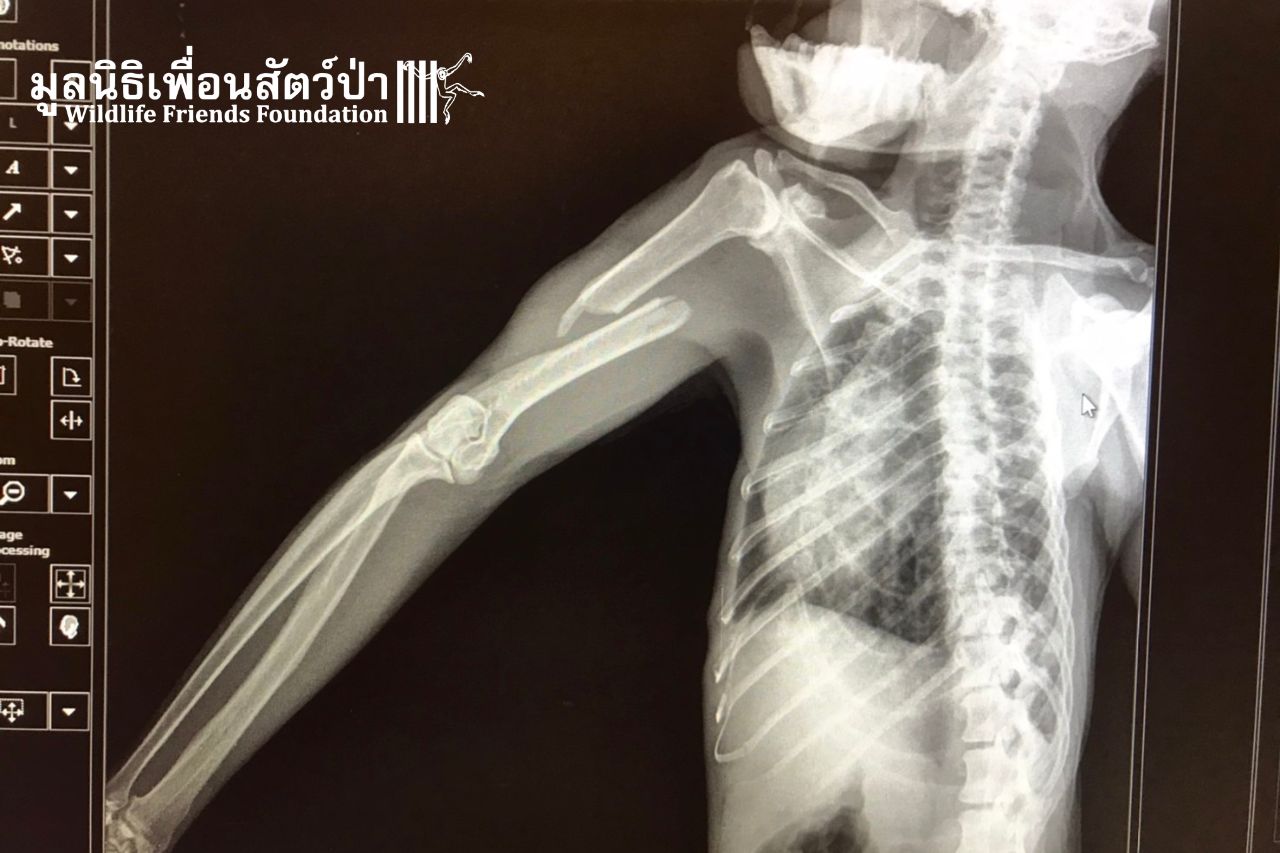

Maprao has a severely broken arm. Perhaps he fell from a tree during a coconut picking session because he was so exhausted. He was found on a farm, confused and in a lot of pain. He still had a chain around his neck. After being beaten and abused his whole life, he is now, thankfully, at WFFT. But every male adult macaque we take in, like Maprao, needs his own enclosure and then, perhaps, he can be integrated with others in the future. We will need at least $2,000 to help Maprao.